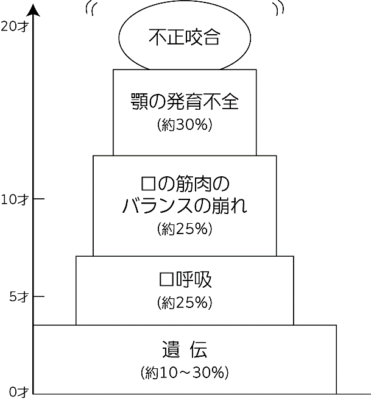

不正咬合の原因は、

小さい頃からの「歯並び」に及ぼす、

悪い習慣の積み重ねにあります。

0歳から3歳頃までは、

遺伝からくる不正咬合が多いですが、

5歳前後より

「口呼吸」「鼻づまり」「口の周りの筋肉が弱いために起こる機能不全」が原因の場合が多いのです。